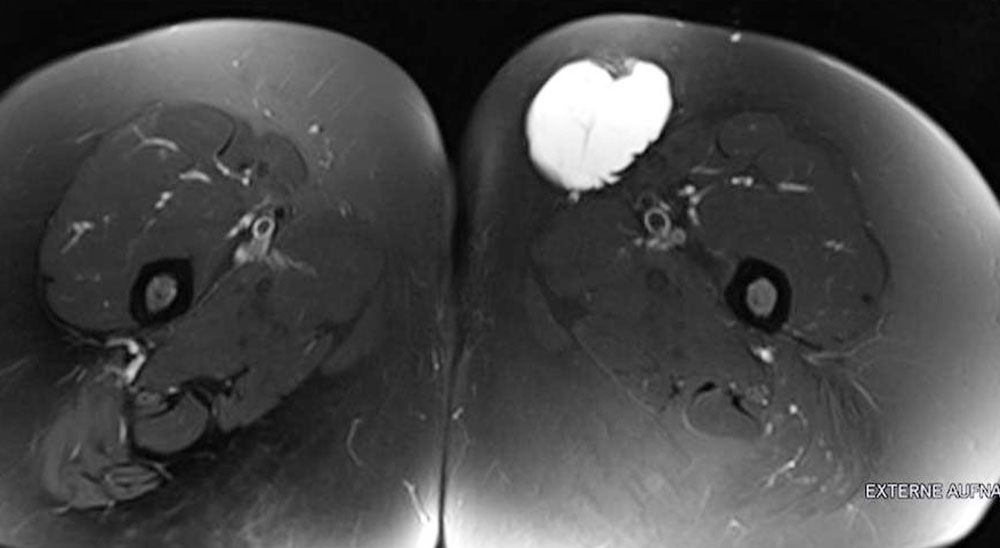

A large retroperitoneal lymphatic malformation may affect bowel passage or bladder capacity and emptying.

In the thigh, a lymphatic malformation can develop between muscle groups and cause displacement, usually without symptoms. An LM in the floor of the mouth between and within the numerous small muscles of the tongue often gives the impression of diffuse infiltration and macroglossia.